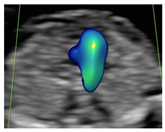

Figure 1.

Case of disagreement in the characterization of color Doppler pattern on the 3VTV between operators 1 and 2 in a case of Ebstein anomaly at 12 + 6 weeks’ gestation. (A,B) show different frames of a videoclip of the 3VTV. (A) Operator 1 observed an abnormal 3VTV pattern in terms of “abnormal vessel number”; (B) operator 2 characterized the same case as with “abnormal vessel dimensions”. AoA, aortich arch; T, trachea; arrow, small pulmonary artery.